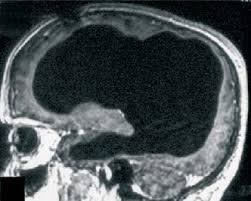

O homem, que não teve o nome revelado, tinha 44 anos quando procurou

um médico por que sentia uma leve fraqueza na perna esquerda.

O médico pediu exames de imagem de seu cérebro e descobriu

que praticamente toda a região que deveria conter tecido cerebral,

na verdade estava cheia de líquido. Apenas uma fina camada do

cérebro se manteve intacto.